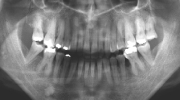

日本矯正歯科学会専門医課題症例(第7症例)

カテゴリー:開咬(overbiteがマイナスのもの)

出題の意味:開咬とは奥歯がしっかり咬んでも(完全に閉じても)、前歯が上下的に重ならないケースを言う。Overbiteがマイナスというのは全然重なっていないということを示しており、マイナス方向に数字が大きくなるほど症状はきつくなる。つまり完全に閉じているのに、前歯の隙間から舌が見えるような状態と言うこと。この症状は、舌や唇の筋力や動かし方に原因があるので、歯を矯正するだけではだめで、舌や唇の動かし方を正常にしないと後戻りを起こしやすい。専門医の試験では、治療後2年以上経過した資料を添付して、経過が良好であることを証明しないといけないので、後戻りしやすいこのケースは難易度が高いといえる。舌や唇の動かし方をトレーニングするのは、医院スタッフ(主に筋機能訓練療法を担当する歯科衛生士)であるので、医療機関の総合力が問われる項目である。

| 初診時